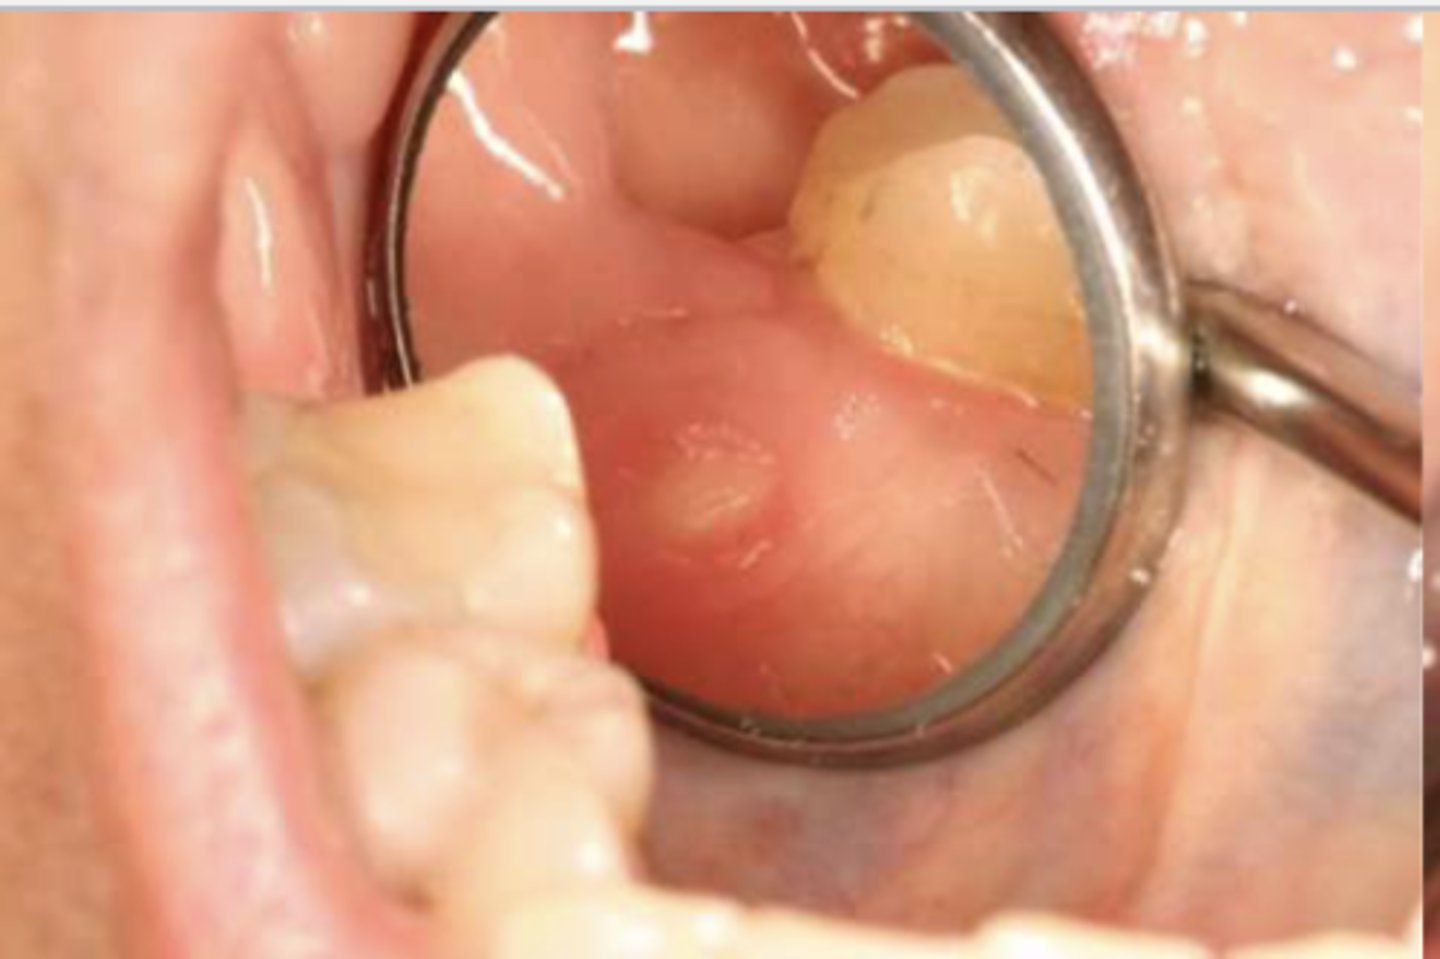

What do you suspect?

epulis fissuratum